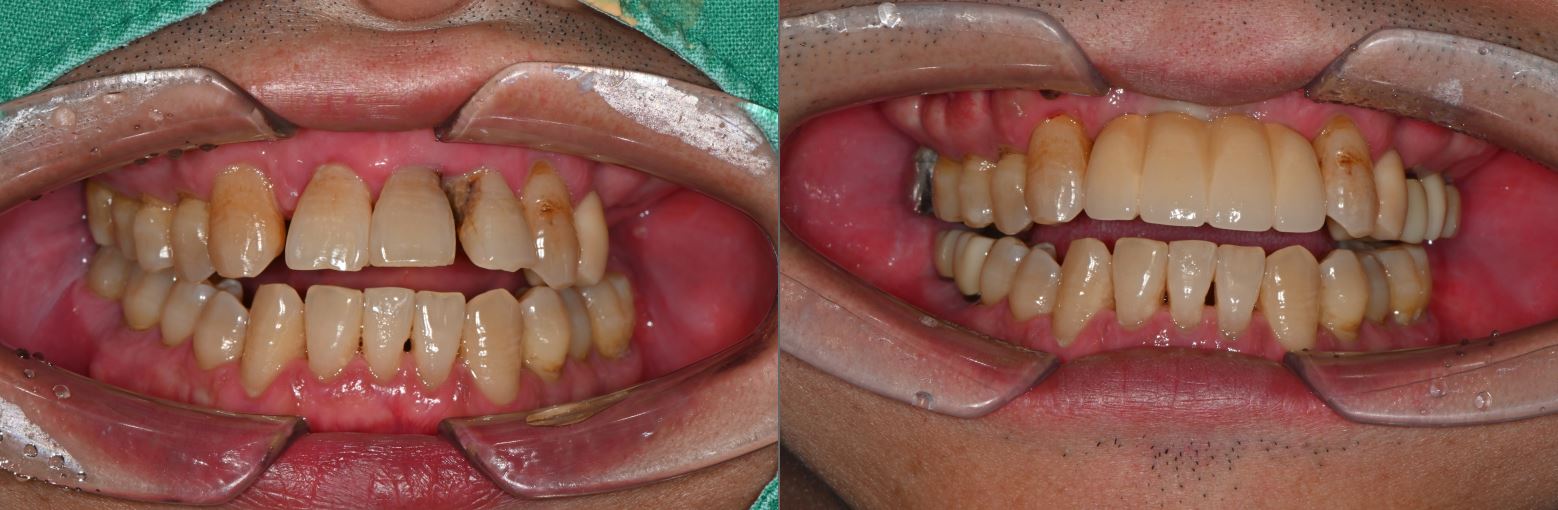

치료전후사진